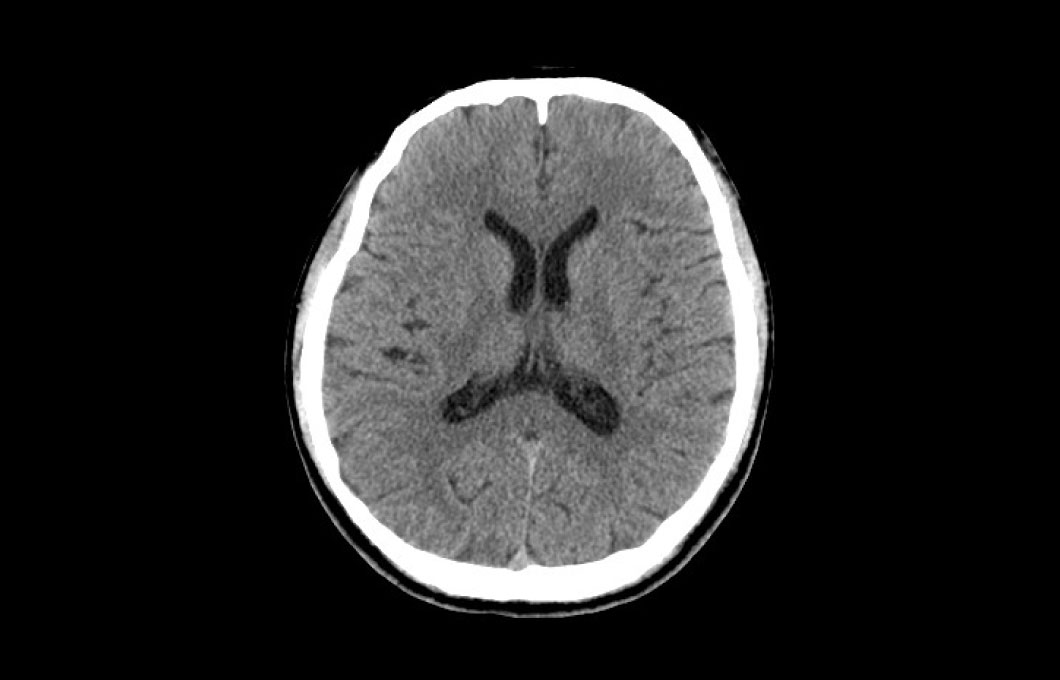

X線とコンピュータを使い人体各部の横断像(輪切り像)を画像にします。脳、肺、肝臓、筋肉等のあらゆる部位・臓器の小さな病変を診断することができます。